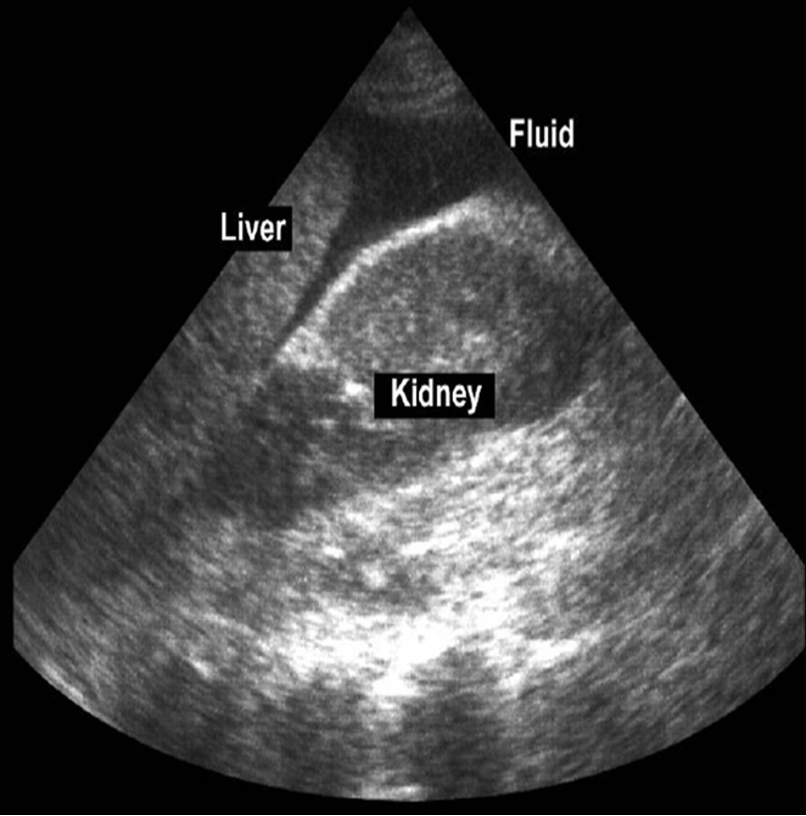

FAST- Focused abdominal sonography in trauma

Rapid & accurate.

Sensitivity up to 99%.

Detects small amount (100 ml) of blood.

Four views:

- Pericardiac

- Perihepatic

- Perisplenic

- Pelvic

Helpful in management of unstable patients.

(Image: FAST)